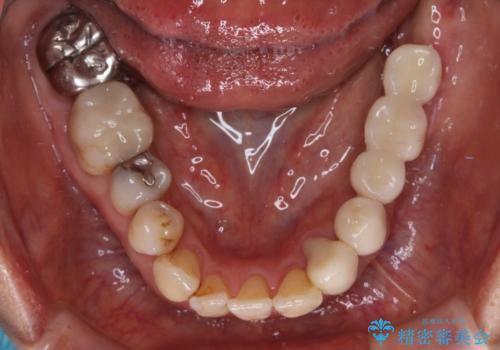

- 義歯を使いたくないものの、骨の幅が狭くインプラント治療を断られているとのことで来院された患者様です。

入れ歯の支台となっていたコーヌスのゴールドも除去し、インプラント部と合わせてオールセラミッククラウンにて補綴治療を行うこととしました。